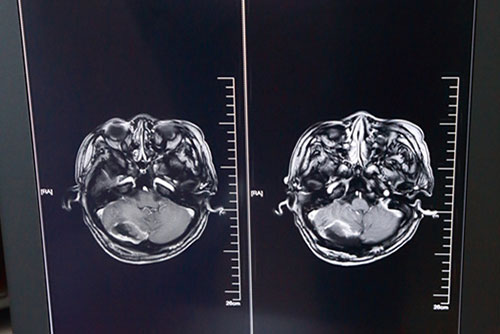

神筆有馬良,神手有侯主任。手術(shù)室內(nèi),無影燈下,切開、上顯微鏡、顱腦手術(shù)導(dǎo)航系統(tǒng)導(dǎo)航.....手持手術(shù)器械的侯主任神態(tài)專注,嫻熟地進(jìn)行每一個手術(shù)步驟,嚴(yán)格按照邊界盡量多的精準(zhǔn)切除腫瘤物。不到4個半小時(shí),手術(shù)順利結(jié)束,腫瘤基本全切,重要腦組織及顱神經(jīng)血管保留完整。術(shù)后一月余,歐女士順利出院,頭痛、走路不穩(wěn)等癥狀明顯改善。

歐女士術(shù)后頭顱MRI影像資料:腫瘤物消失